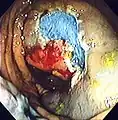

The first step is usually a digital rectal examination (DRE), to examine the tone of the anal sphincter and to determine if preparation has been adequate. A DRE is also useful in detecting anal neoplasms and the clinician may note issues with the prostate gland in men undergoing this procedure.[55] The endoscope is then passed through the anus up the rectum, the colon (sigmoid, descending, transverse and ascending colon, the cecum), and ultimately the terminal ileum. The endoscope has a movable tip and multiple channels for instrumentation, air, suction and light. The bowel is occasionally insufflated with air to maximize visibility (a procedure that gives the patient the false sensation of needing to take a bowel movement). Biopsies are frequently taken for histology. Additionally in a procedure known as chromoendoscopy, a contrast-dye (such as indigo carmine) may be sprayed through the endoscope onto the bowel wall to help visualize any abnormalities in the mucosal morphology. A Cochrane review updated in 2016 found strong evidence that chromoscopy enhances the detection of cancerous tumors in the colon and rectum.[56]

Polyp is identified.

A sterile solution is injected under the polyp to lift it away from deeper tissues.

A portion of the polyp is now removed.

The polyp is fully removed.